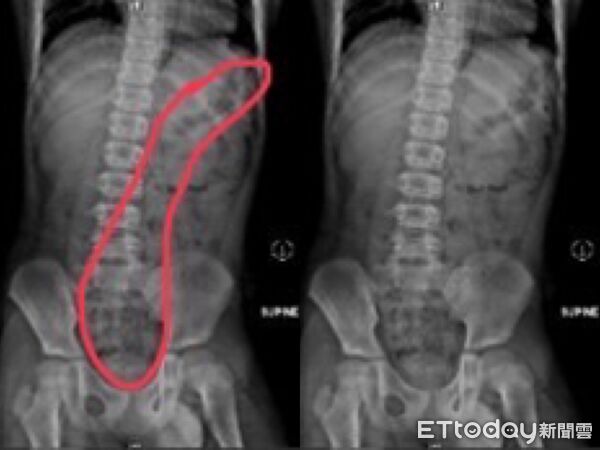

▲小五男童上廁所不專心,滿肚子都是屎。(圖/記者許宥孺翻攝)

收治病例的阮綜合醫院急診兒科主治醫師蕭宇超分享,近期急診出現多例兒童便秘案例,一名11歲小五男童被送到急診時,嘴唇嚴重發紫、手腳冰冷狂冒冷汗,男童狂喊肚子痛,經問診、觸診及腹部X光檢查後診斷是嚴重便秘,積糞都快塞到胸部位置去,經過灌腸後,男童解出很多大便,症狀也隨即緩解。媽媽說,男孩習慣邊大便、邊玩手機,都是被罵上太久才匆忙沖馬桶、從廁所出來,自己也都不清楚是否有大出來或有沒大乾淨。